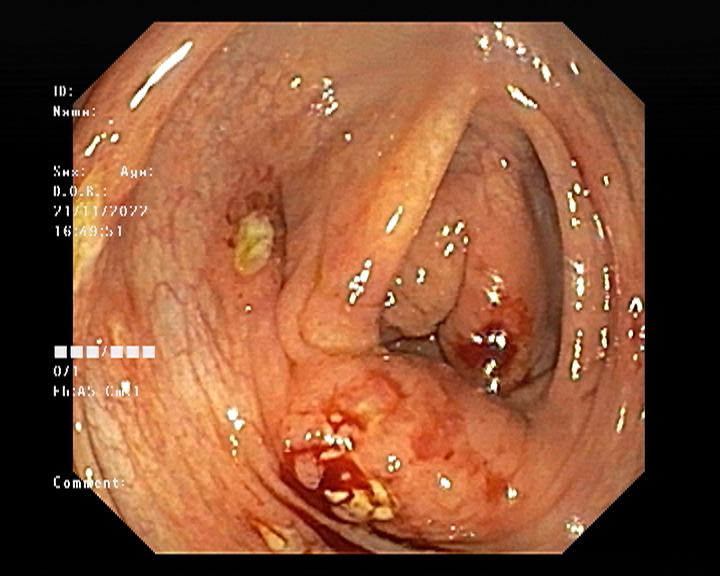

Endoscopy and colonoscopy are safe and accurate procedures used to directly examine the digestive tract and detect the root cause of chronic acidity, GERD, abdominal pain, bleeding, and bowel irregularities. These minimally invasive tests help identify ulcers, inflammation, infections, polyps, strictures, and early cancerous changes.

At Sapphire Gastroenterology Center, modern endoscopic equipment ensures precise diagnosis and, when required, therapeutic intervention during the same procedure. Based on findings, targeted treatment plans are created, including medication, diet guidance, and preventive strategies. Early diagnosis through endoscopy and colonoscopy plays a crucial role in preventing serious complications and improving long-term digestive health.